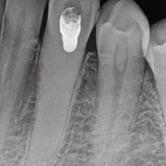

Calcificación Pulpar

La calcificación pulpar es la formación de depósitos de calcio dentro de la pulpa dental, que puede dificultar el tratamiento de conducto.

Los pacientes generalmente no tienen síntomas, pero pueden experimentar sensibilidad.

El tratamiento incluye la eliminación de los depósitos durante el tratamiento de conducto. Es importante tratarlo para evitar complicaciones durante el procedimiento.